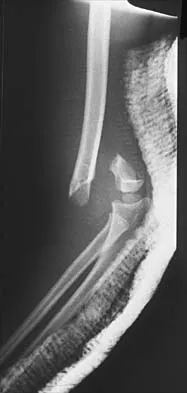

Figure 43 shows the lateral radiograph of a 12-year-old boy with mild osteogenesis imperfecta who injured his left elbow after pushing his brother. Treatment should consist of

Explanation

The patient has a displaced fracture of the apophysis of the olecranon for which most authorities recommend surgical treatment. In older children, stability of the reduction may be achieved by the use of two parallel medullary Kirschner wires and a figure-of-8 tension band loop of either stainless steel wire or absorbable suture. The use of an absorbable suture does not require removal of the implant. Absorbable suture alone is best used in very young patients who have this type of injury. An intramedullary screw would pose an unnecessary risk of future growth disturbance. A displaced, isolated fracture of the apophysis of the olecranon is an unusual injury in a child. It has been suggested by several authors that children who have osteogenesis imperfecta may be especially prone to this injury. One study reported seven of these fractures occurring in five children who had the mild form of osteogenesis imperfecta (Sillence type IA). The authors of this study suggest that the diagnosis of osteogenesis imperfecta be considered in any child who has a displaced fracture of the apophysis of the olecranon, especially when the injury is associated with relatively minor trauma. Stott NS, Zionts LE: Displaced fractures of the apophysis of the olecranon in children who have osteogenesis imperfecta. J Bone Joint Surg Am 1993;75:1026-1033. Gaddy BC, Strecker WB, Schoenecker PL: Surgical treatment of displaced olecranon fractures in children. J Pediatr Orthop 1997;17:321-324.